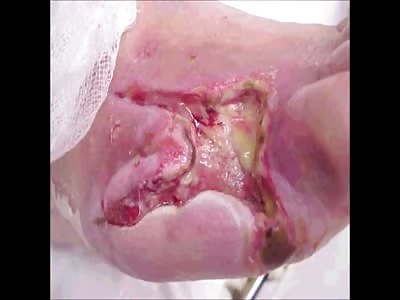

This was a 62-year-old man with type 2 diabetes who was assaulted with a wooden plank and rusty nail on his frontal scalp area sustaining a laceration 3 days prior. The laceration was sutured and a head injury was ruled out with a CT scan.